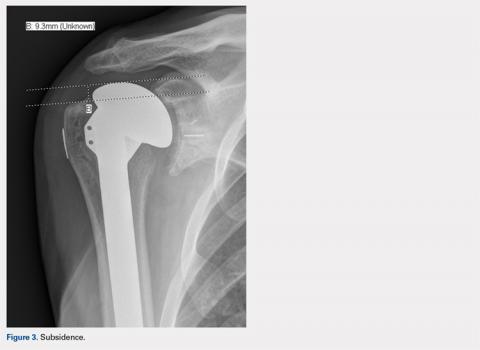

Subsidence of the prosthesis was calculated by determining the difference between immediate postoperative heights of the prosthesis in comparison to the value of the final follow-up films. To calculate the height, 2 lines were drawn, 1 line was drawn perpendicular to the top of the prosthetic head and 1 perpendicular to the top of the greater tuberosity (Figure 3).

This distance was measured both immediately postoperatively and at final follow-up. The height difference between the 2 time points was used to calculate the subsidence.